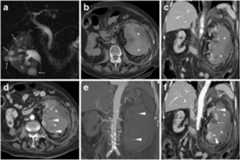

Fig. 2.

A 56-year-old Chinese man with hypertension, diabetes and chronic kidney failure undergoing regular haemodialysis suffered from acute abdomen pain with hypotension. Unenhanced (a), corticomedullary (b) and nephrographic (c) multidetector CT acquisitions showed a large left-sided subcapsular renal haematoma (*) and typical features of ESRD, including small cortical cysts (thin arrows). Note the minimal associated perirenal and posterior pararenal bloody effusion (+ inc). Focal CM extravasation consistent with active bleeding was detected by CT (arrowhead inb) and confirmed at selective renal angiography (arrowhead ind), originating from a distal arterial branch at the lower half of the kidney. Angiography revealed severe luminal irregularities of all renal arteries and allowed occlusion of the left renal artery with an 8-mm Amplatzer vascular plug (AGA Medical Corp., Plymouth, MN:short arrows ine) distally to the inferior adrenal artery. Follow-up CT (f) confirmed the Amplatzer plug in site (short arrow) and stopped haemorrhage